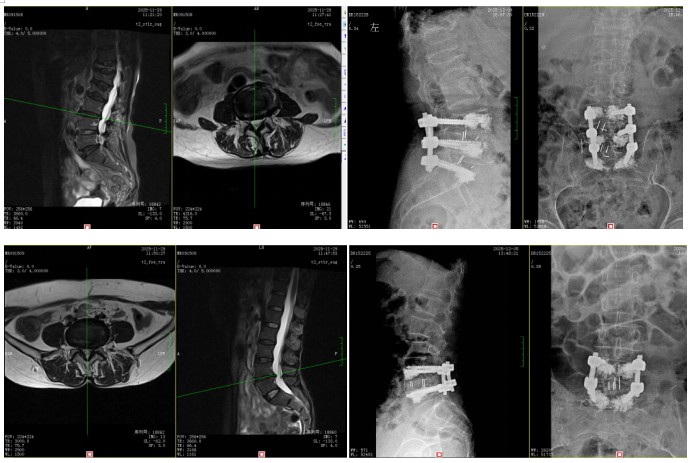

輾轉(zhuǎn)多地求醫(yī),她們了解到衡陽市中心醫(yī)院脊柱外科錢軍博士在治療腰椎間盤突出方面經(jīng)驗(yàn)豐富,母女倆便一同找上門來。錢軍博士詳細(xì)詢問了病史,并為她們進(jìn)行了系統(tǒng)的體格檢查和影像學(xué)評(píng)估。結(jié)果顯示,唐奶奶是腰4/5、腰5/骶1節(jié)段椎間盤突出,嚴(yán)重壓迫椎管內(nèi)神經(jīng)及右側(cè)神經(jīng)根受壓;王女士則是腰5/骶1節(jié)段椎間盤突出,左側(cè)隱窩狹窄,神經(jīng)根受壓明顯。兩人均符合手術(shù)指征。

“腰椎間盤突出壓迫神經(jīng)根,就像石頭壓住了水管,不通則痛,還會(huì)導(dǎo)致下游‘田地’(腿部肌肉)缺血‘營養(yǎng)不良’,出現(xiàn)麻木、乏力。”錢軍博士用形象的比喻向母女倆解釋了病情,“當(dāng)保守治療無法搬開‘石頭’時(shí),就需要手術(shù)來徹底減壓?!笨紤]到兩位患者的年齡、身體狀況和病變特點(diǎn),錢軍博士團(tuán)隊(duì)進(jìn)行了深入的術(shù)前討論,為她們分別制定了精準(zhǔn)的手術(shù)方案。手術(shù)的核心目標(biāo)是在充分解除神經(jīng)壓迫的同時(shí),最大程度減少創(chuàng)傷,保護(hù)脊柱穩(wěn)定性。通過精密的操作,成功摘除了壓迫神經(jīng)的突出髓核組織,解除了神經(jīng)根的“枷鎖”。